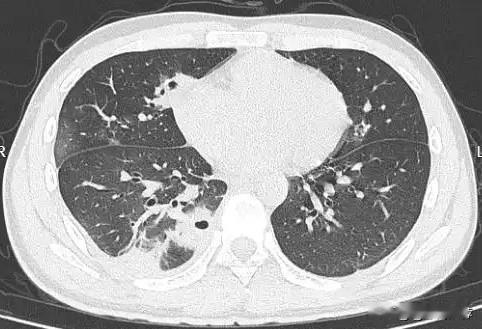

挤一颗痘痘竟致肺里现十几个空洞!大二学生的惨痛教训 20岁的大二学生小林为备考熬夜后,脸部冒出一颗黄豆大小的红肿痘痘。因觉得影响美观,他未洗手便对着镜子将其挤掉,当时看着脓水流出还倍感清爽。 然而几天后,痘痘不仅持续化脓,小林还出现发烧、咳嗽、咳痰等症状,退烧药仅能暂时缓解不适,右下胸更是传来针刺般的疼痛,深呼吸、咳嗽时疼得直冒冷汗。熬至第三天,体温升至39℃的小林紧急前往宁波大学附属第一医院就诊。 接诊的丁群力主任医师通过CT检查发现,小林肺内出现十几个空洞,部分肺组织已坏死,确诊为血源性肺脓肿。细菌培养和基因检测显示,其血液中检出的金黄色葡萄球菌是“元凶”——该细菌原本存在于皮肤表面,而小林挤的痘痘位于脸部“危险三角区”,未洗手的操作让细菌在挤压压力下进入血管引发败血症,进而随血流侵入肺部,侵蚀肺组织导致严重感染。医生提醒,脸部危险三角区的痘痘切勿随意挤压,皮肤出现感染需及时科学处理,避免引发致命风险。